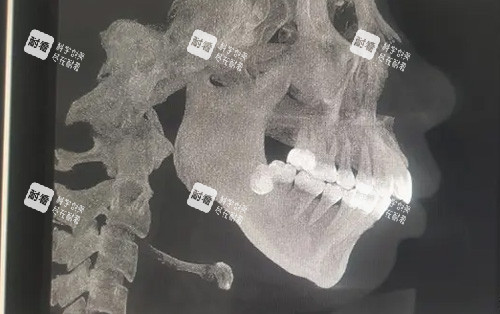

2. 齐全的术前检查

影像学检查:CT、X线片等。

牙模制作与分析。